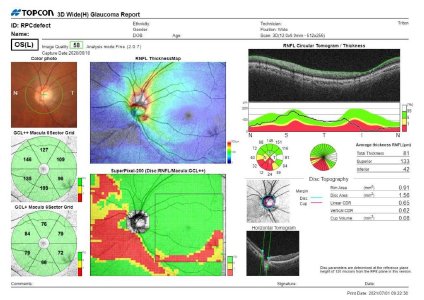

トプコン トリトン

3次元眼底像撮影装置

主な特徴

・スキャン光が見えない、中心波長1,050nmのSSOCT

・100,000Aスキャン/秒

・マルチモダルOCT(カラー眼底/レッドフリー/OCT/FA/FAF/OCT-A/前眼部撮影)

・SS OCT Angiography、広角パノラマOCT-A撮影

当緑内障疾患や網膜疾患など幅広い眼疾患の早期発見や病状の分析にかかせない検査機器です。

精細な画像診断が可能なので網膜の微細な病変も見逃しません。

症例ごとにいろいろなレポートを作成することにより医師が診断においても具体的になり診察で前回との症状の違いなどの説明がスムーズです。